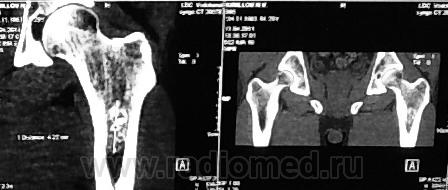

1. Остеосцинтиграфия: Единичный очаг гиперфиксации визуализируется в головке плечевой кости справа.

2. На рентгенограмме правого плечевого сустава (рентгенограмма №1) в проксимальном метафизе и метадиафизе плечевой кости определяется участок уплотнения и груботрабекулярной перестройки костной структуры с неровными, но довольно четкими контурами. Вокруг участка костная структура разрежена.

Заключение:

Мнение врача-рентгенолога: рентгенологическая картина не похожа на опухолевое поражение. Вероятно, имеет место остеосклероз, возможно, вследствие травмы или инфаркта кости. Если дифференцировать между опухолевым поражением, то вероятнее первичная доброкачественная опухоль (остеобластома?) правой плечевой кости, метастаз – мало вероятно, метастаз рака почки – не вероятно!